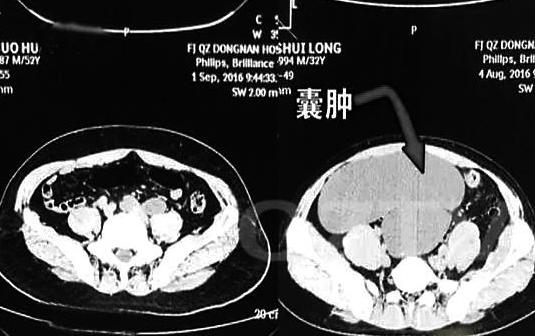

上图中左侧是正常人的腹腔,右侧是雷先生的腹腔,图中可以看出,其腹腔2/3的空间被肿大的输尿管占满,形成了囊肿,随时可能破裂,所以医生决定,迅速对雷先生进行手术,切除右侧重复肾脏和病变的输尿管。

医生说,切除的囊肿竟然重达5斤多。